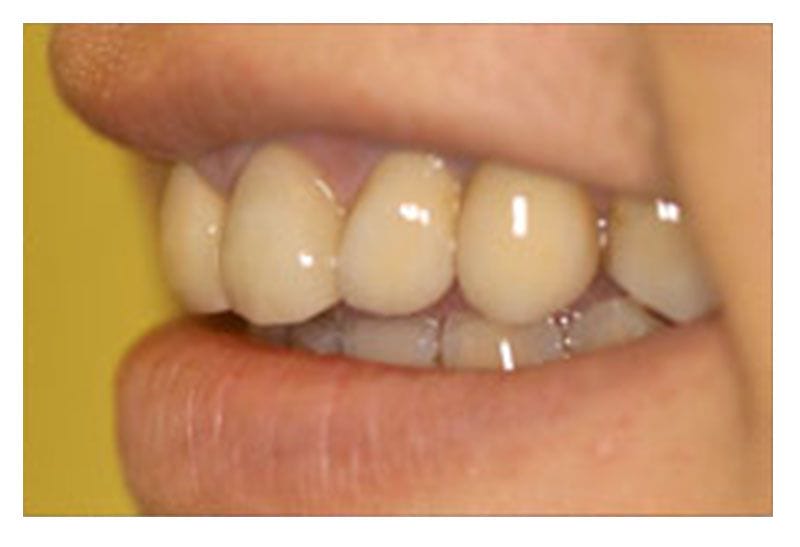

治療後-口外側面